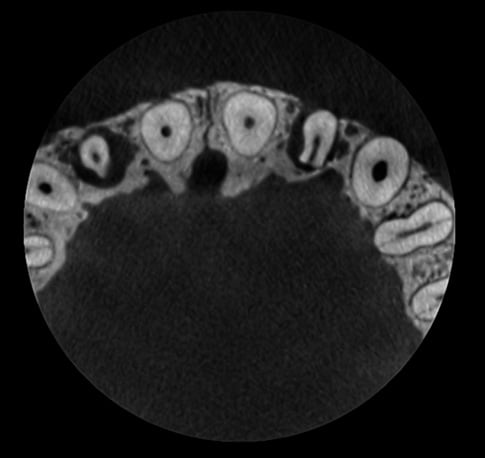

Bez redukcji szumów

Po użyciu filtra szumów Planmeca AINO

Planmeca ProMax 3D s Ø50x50 mm, rozmiar woksela 75µm

Planmeca ProMax 3D Mid Ø40x50 mm, rozmiar woksela 75µm